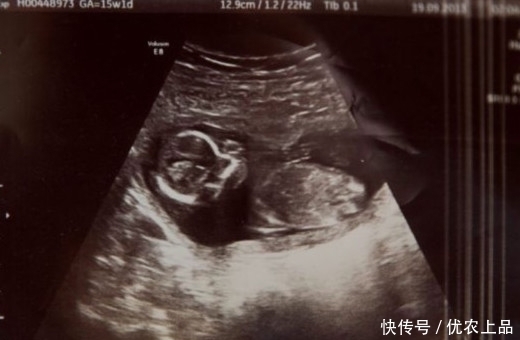

【胞胎姐妹被妈妈用药物流掉,她却在母亲腹中安稳存活】在手术前,医生在她腹部监测到不属于她的另外一个心跳,原来米歇尔怀的是双胞胎,其中一个宝宝被服用药物流掉了,另一个却奇迹般的活了下来。

米歇尔把她生了下来,取名梅甘。

在梅甘之前,她还有一个儿子一个女儿,现在她们三姐弟妹团圆。

姐姐现在4岁,哥哥2岁,她们都非常疼爱梅甘这个可爱的小妹妹。

米歇尔一家5口全家福。